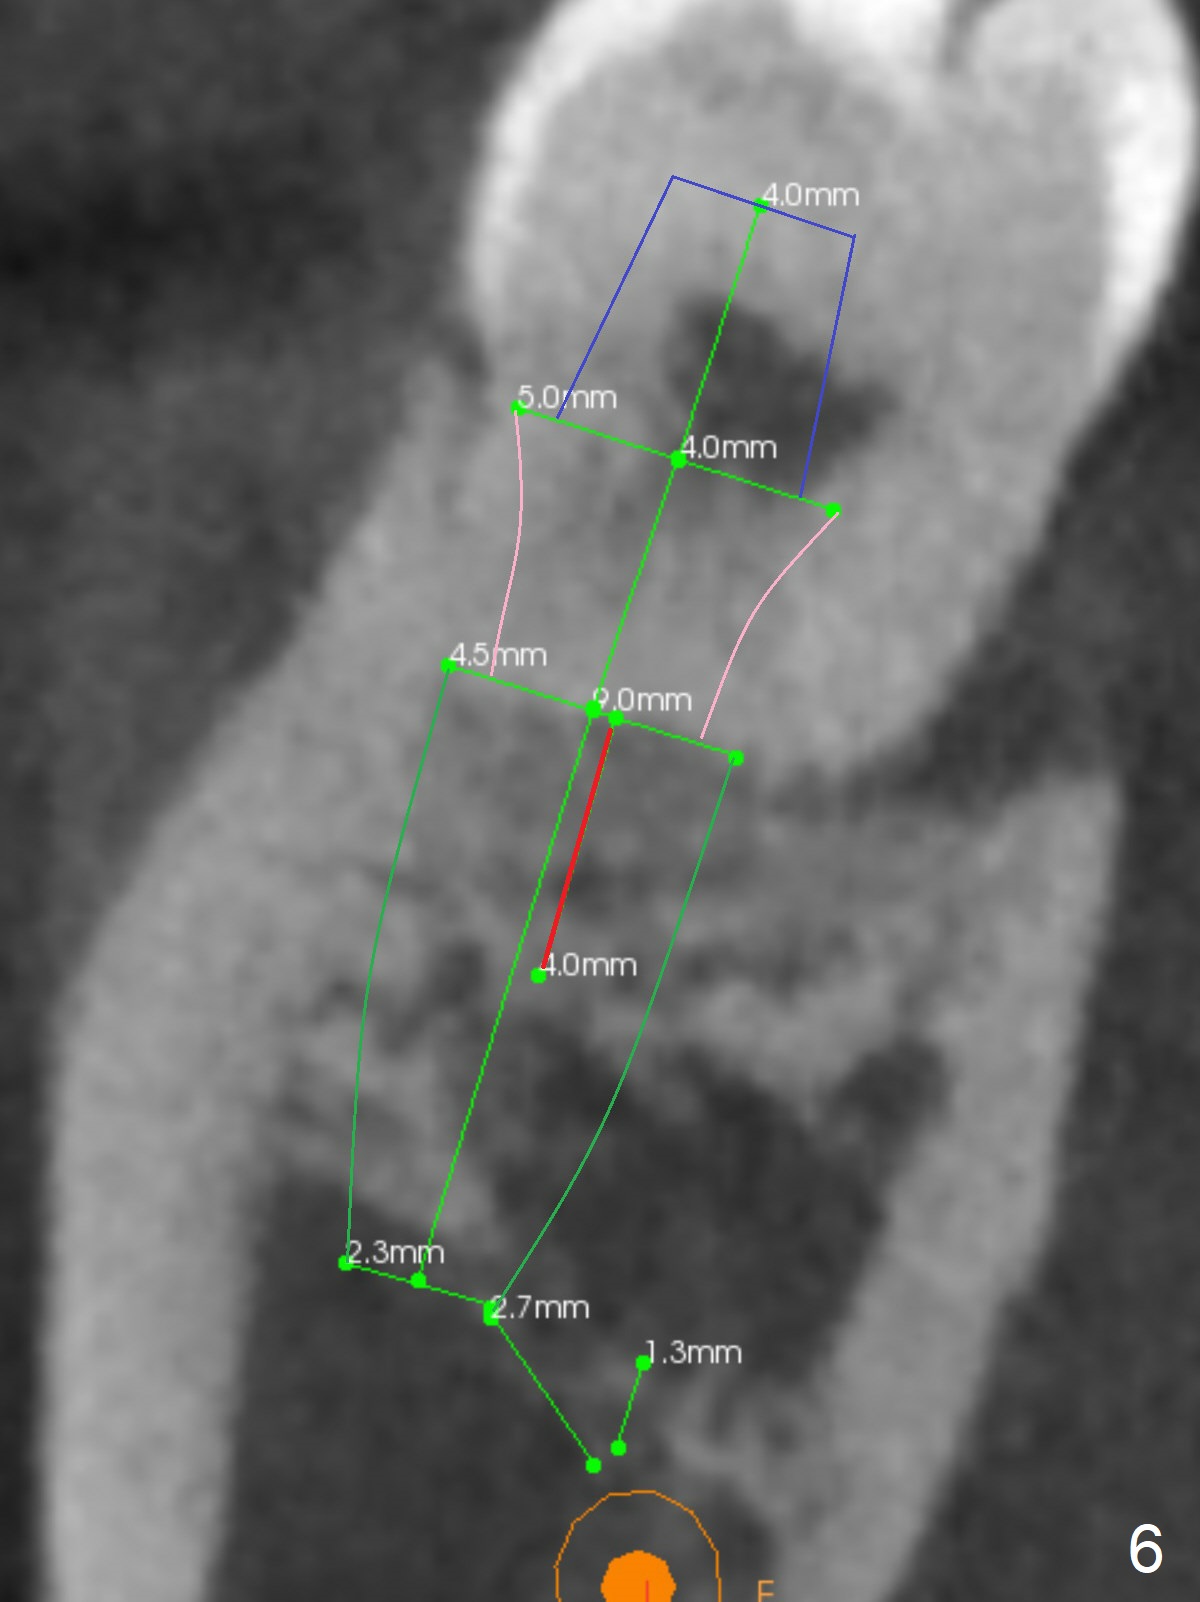

A 40-year-old man removes food debris from the lower left area, probably between #17 and 18, using Water Pik. Initially it looks as if the bone loss lingual (Fig.1 (CBCT with 3 sections) L) to #18 is derived from #17 (red curved arrow). Closer look shows generalized thickened periodontal ligament space at #18 (Fig.2 arrowheads). The patient requests extraction of the tooth #17; the tooth #18 seems non-salvageable. When an immediate implant is placed in the middle of the socket (Fig.3,4 (coronal section)), there is limited amount of the native bone to stabilize the implant (~1 mm). In contrast, there is approximately 5 mm of the native bone for primary stability if the implant is placed in the mesial slope of the fused socket (Fig.5 yellow dashed line). The implant should be placed buccally (B) to reduce the chance of nerve injury (Fig.4,6).